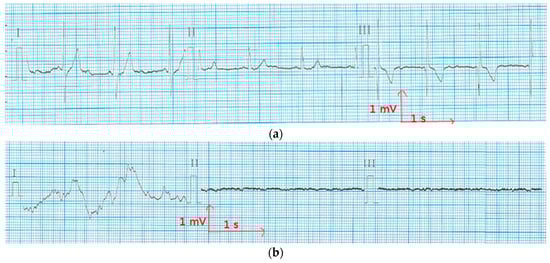

Figure 7.

Electrocardiography at rest from the polyester electrode (a) before washing; and (b) after 50 washing cycles.

In order to reduce muscle movements and respiratory artifacts, as a first measurement, the volunteer was sitting at rest. This position allows obtaining high-quality signals that can be used to detect heart function anomalies. The above ECG measurement tests conducted for static postures were recorded successfully with no prior skin preparation or application of conductive gels. With the cotton and polyamide electrodes, decent ECG signals were obtained for medical analysis. Figure 5 and Figure 6 show that before and after 50 washing cycles, the P and Q wave and QRS complex corresponding to the different phases of polarization and depolarization of cardiac cells were easily observed in the signals recorded using both the cotton and polyamide electrodes. The ST (the ST segment is the interval between S and T waves; it is important to have a clear view of it to track ischemic issues) segment was also observed, which is very important for myocardial ischemia and ventricular arrhythmias detection. However, for the polyester-based PEDOT:PSS-coated electrodes (Figure 7), P, QRS, and T waves were not recognizable; therefore, the acquired signals from the polyester electrodes were not acceptable for our application. This failure is due not only to the lower quantity of PEDOT:PSS absorbed by polyester, but also to the high contact impedance between the skin and the polyester electrode.

In ECG measurement, the quality of ECG signals depends on the contact impedance between the body and the wearable electrodes. This contact is liable to drop because of a change in motion or posture. In Figure 8 and Figure 9, there are three ECG signals recorded (a) at rest, (b) walking, and (c) climbing stairs. In all of the cases, lead I is relative to the signal recorded from the two chest electrodes, lead II between the right chest electrode and the left leg electrode, and lead III between the left chest electrode and the left leg electrode. It is obvious that the signal quality is best when only the two chest electrodes are used, particularly in motion. This case is the best for our application, as the ECG signal should be recorded only using the underwear. As it can be seen from Figure 8, using polyamide electrodes subjected to 50 washing cycles, the lead I of ECGs taken with the polyamide electrodes have stable P, R, and T wave amplitudes, indicating that the influence of motion is significantly lower on the recordings of these electrodes. Leads II and III exhibit some variation in amplitudes and are more contaminated by noise because, while walking and climbing stairs, the crocodile clip connected to the metallic medical electrodes on the legs tends to move. However, P, QRS, and T waves are still recognizable in lead I. Thus, the acquired signals are acceptable for our application. Figure 9 shows that with the cotton electrodes put through 50 washing cycles, at rest, the signal is quite good. However, during motion tests, the signals are not acceptable as P, QRS complex, and T waves are not detectable. This failure is due to the poor connection between the crocodile clips and the ECG device. We can also conclude that the surface resistivity of the electrode does not play an important role for the ECG recording, because after the washing process, the cotton electrodes with lower surface resistivity had worse ECG signals compared to the polyamide electrodes. We suppose that the contact impedance between the electrode and the skin is another factor that impacts the ECG recording.